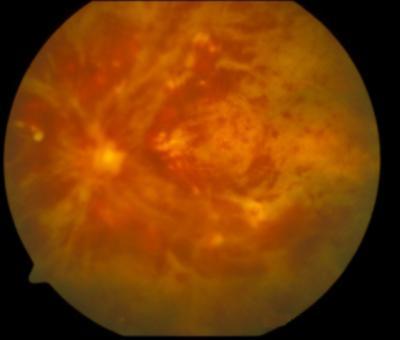

retinal vein occlusion

Central retinal vein occlusion